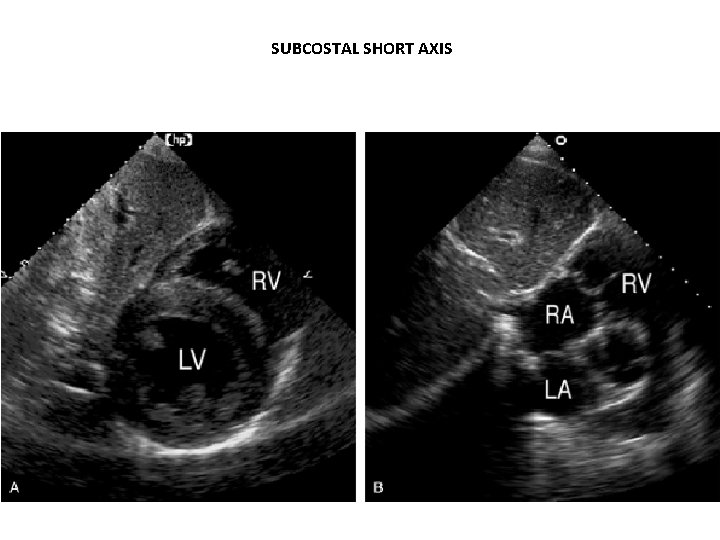

SUBCOSTAL SHORT AXIS